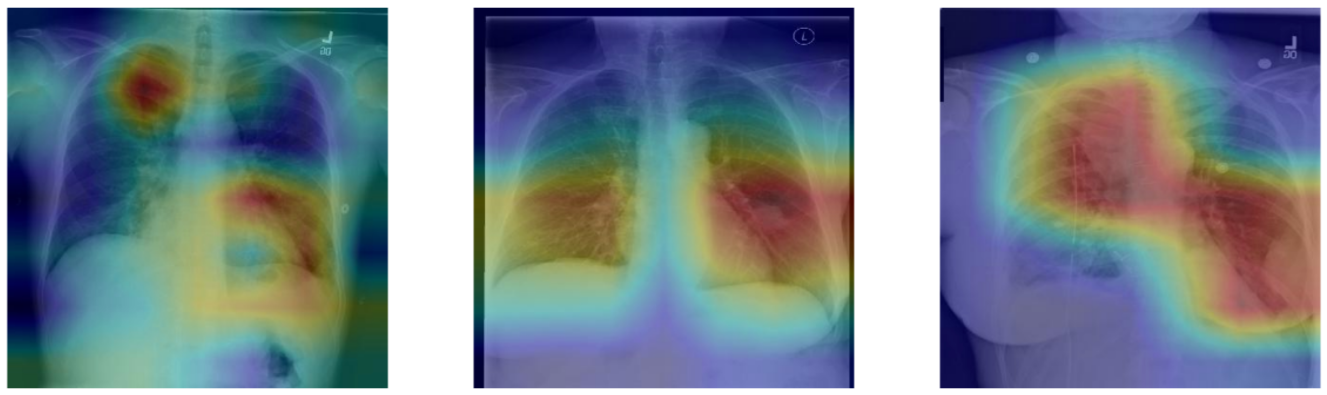

: 환자 32,717명의 108,948개 frontal-view X-ray 이미지가 포함된 ChestX-ray8 데이터셋을 사용

→데이터셋의 각 이미지에는 14개의 병리학적 상태를 식별하는 여러 텍스트 마이닝 레이블이 포함됨

*의사는 이 결과를 통해, 8가지 질병을 진단하는데 사용할 수 있음

→이 데이터에 기반하여 14개의 레이블이 지정된 병리 상태에 대한 분류 모델을 개발할 것

*각 병리에 대해 '양성' 또는 '음성'을 예측

: 이 데이터셋은 14개 병리 상태 중에서 아래 5개에 대해, 방사선과의사가 합의하여 주석을 달았음

- Consolidation

- Edema

- Effusion

- Cardiomegaly

- Atelectasis